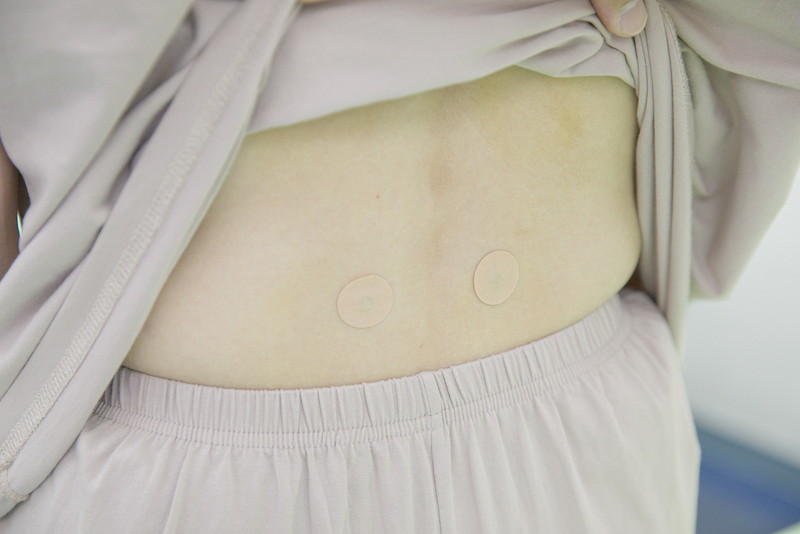

そこで当院では検査を行い、インナーユニットに原因がある場合はハイボルト療法やCMC筋膜ストレッチ、トレーニング指導を行います。

そしてバネ指に関しましては患部に対してのハイボルト療法やテーピングなどに加えて、首・肩関節を正しく使えるようにするための手技療法を行います。

また、自律神経に原因がある場合は炭酸ヘッドスパ(THS)やHOT腸もみ、CMCはり施術などホルモンバランスや体内リズムを整える施術を行います。